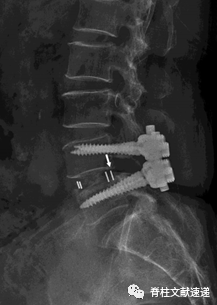

该文献旨在探索出TLIF术后cage移位(CM)和cage退回(CR即cage移位至椎管内)的危险因素,对784位(共881个节段)行TLIF术的患者进行随访与观察,术后共有56个节段发生了cage移位CM(6.4%),其中17个节段(30.4%)被认定为cage退回CR,17.9%的CM患者和0%的CR患者cage位置靠前,而82.1%的CM患者和100%的CR患者cage位置靠后(OR=6.45,P=0.04)。

因此作者认为cage放置位置靠后,是cage移位(CM)和cage退回发生的重要危险因素,此外作者还发现骨质疏松症、术中终板的损伤、梨形的椎间盘和术中只使用一个cage也与CR和CM的发生相关。

图注:上图为术后即刻X线片,下图为术后3个月X线片,可以看出该患者术后3个月时cage移位到了椎管内,即发生了cage退回(CR)。